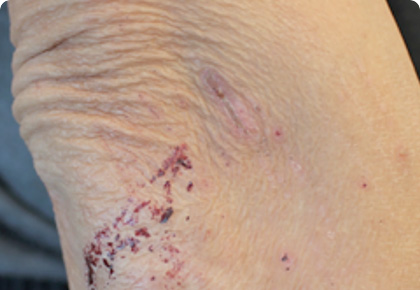

아토피 증상과 특징

아토피는 각 환자에 따라 다양한 증상과 정도에 차이가 있어,

정확한 진단을 받는 것이 무엇보다 중요합니다.

진물

노폐물이 배출되지 못하고 쌓이다가 피부

염증으로 세포가 손상되며 나타나는 증상

가피

노폐물이 배출되지 못하고 쌓이다가 피부

염증으로 세포가 손상되며 나타나는 증상

찰상

피부 표면이 문질려서 살갗이 벗겨지는 증상

2차 감염

만성화된 아토피와 무분별한 면역억제제 사용으로 인해

바이러스, 박테리아, 곰팡이균에 감염된 전신 증상